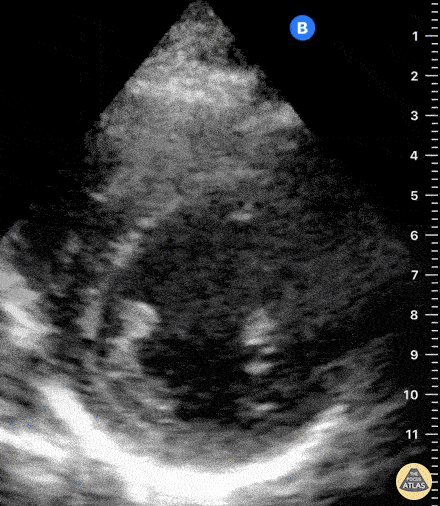

Normal Cardiac Anatomy - Normal Parasternal Short Axis View

Normal PSAX view at a level of the papillary muscles. In the center of the screen is the muscular walled LV, which forms a perfect circle. The smaller, thin-walled RV is seen superficially and wrapped around the LV. Dr. Felipe Urriola, Puerto Aysen Hospital, Emergency Department, Chilean Patagonia.